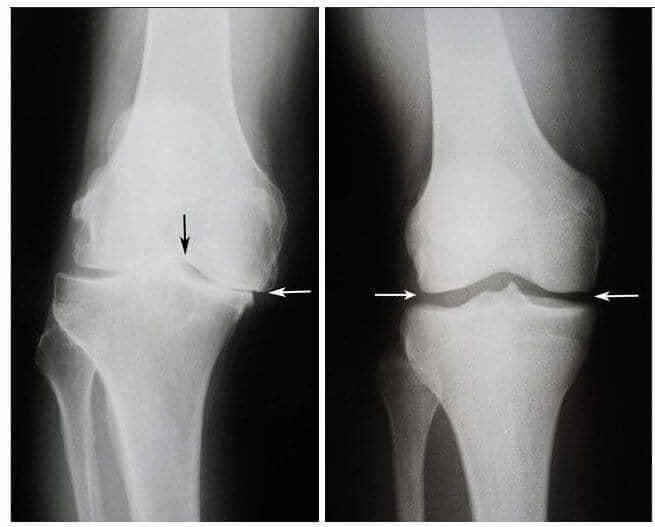

Тоді сталося диво. Після повного огляду лікар дав Валентині ці самі капсули про які всі говорять та наказав приймати щодня рано перед сніданком та перед сном. Через кілька тижнів вона змогла самостійно встати з інвалідного візка та піти до лікаря. Через шість тижнів ренгенні знімки показали що суглоби Валентини вдалось повністю вилікувати від остеоартриту.

Знімок колінного суглоба Валентини до і після лікування

Ліворуч: Знімок до лікування - хрящова тканина повністю зруйнована. Рекомендація лікаря – операція та заміна суглоба.

Праворуч: Знімок після лікування капсулами Ortorion - суттєве поліпшення стану суглоба.